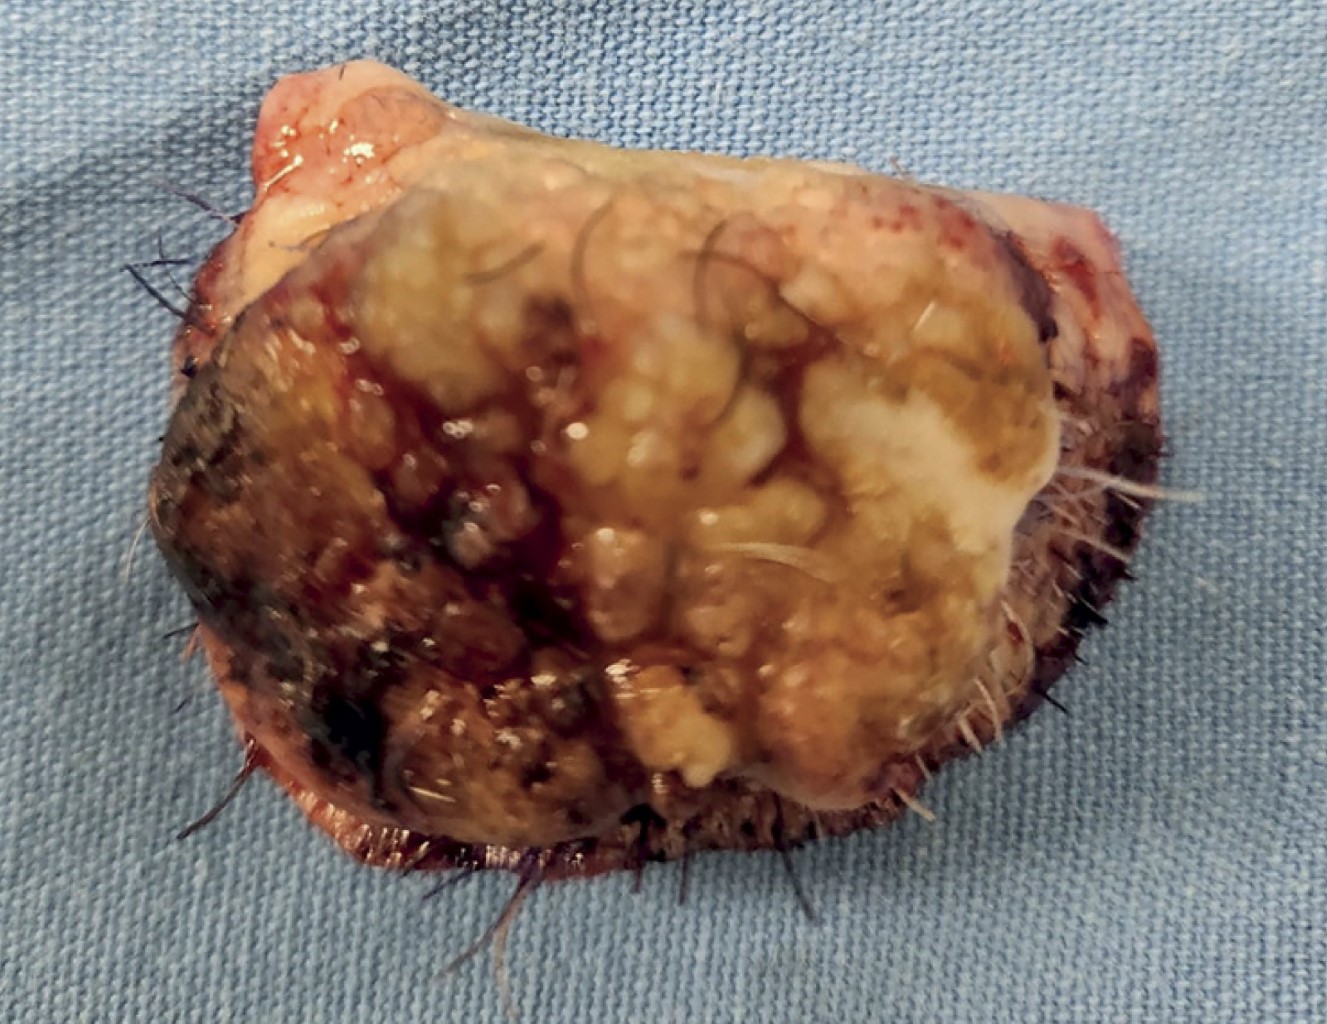

Bajo anestesia general con intubación nasotraqueal, previo marcaje de la lesión con bordes de 6 mm, marcaje de surcos labiomental y nasogenianos se diseñó colgajo Karapandzic según la técnica descrita, previa infiltración con lidocaína a 2% con epinefrina en dilución 1:100,000 (Figura 2). Se resecó la lesión marcada dejando márgenes libres, posteriormente se continuó con incisiones del colgajo de forma semicircular en piel, tejido celular subcutáneo, músculo orbicular de los labios y mucosa a nivel del surco labiomental (Figura 3). Se siguió con incisión de la porción cefálica del colgajo, únicamente piel y tejido celular subcutáneo, para preservar las ramas del nervio bucal, siguiendo como referencia los surcos nasogenianos. Con disección roma se identificó el músculo y su pedículo de la arteria labial inferior, Después de la liberación completa de los colgajos, se transpusieron ambos colgajos hacia medial en dirección al borde del defecto en el labio inferior y se verificó que permitiera un cierre sin tensión de los tejidos. Se realizó una incisión en el borde inferior lateral derecho para compensar los excesos; se verificó la hemostasia y se cerraron por planos la mucosa, el músculo orbicular de los labios y piel (Figura 4). La pieza se envió a patología (Figura 5).

Se dio seguimiento por la consulta, con citas a la semana, tres semanas del postoperatorio, al cumplir un mes y seis meses (Figura 6). El reporte de patología se dio con diagnóstico histopatológico de CCE (Figura 7). Después de un adecuado proceso de cicatrización, el paciente presenta una línea blanca y roja labial con continuidad, sin afectaciones sensitivas, musculares o nerviosas; apertura bucal sin microstomía ni limitación en la alimentación o el habla (Figura 8).

Figura 5